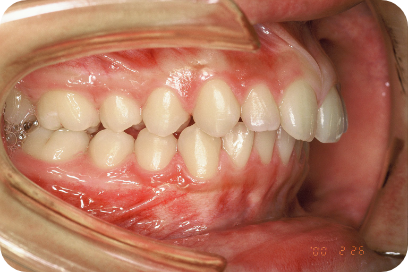

Tさん

Before

After

- 形態:狭いV型の上顎を丸くて広いU型に改善、歯ならび、咬み合わせの改善

- 機能:咀嚼嚥下トレーニング、口腔周囲筋トレーニング、姿勢改善